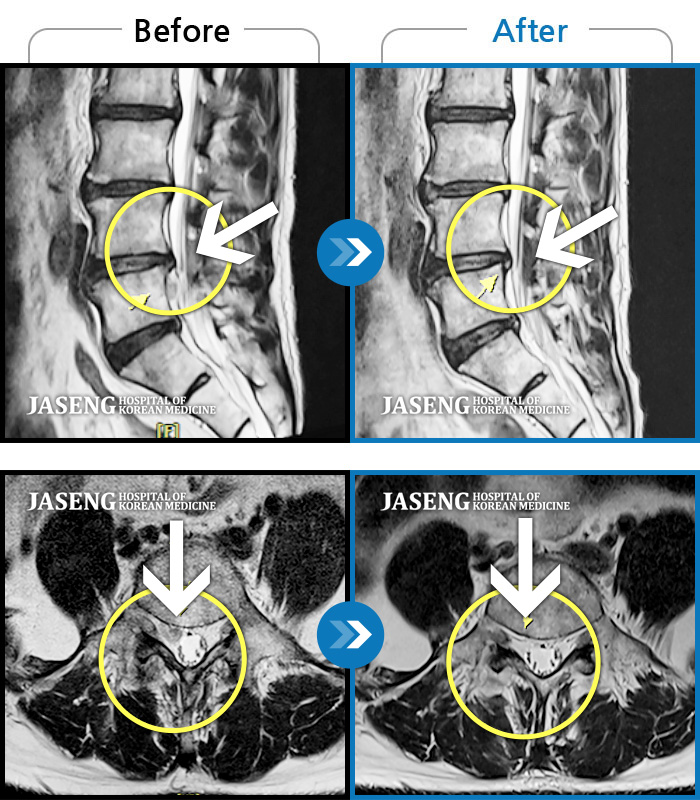

허리디스크

광주 · 김동은 원장

양측 허리부터 양측 골반까지 당기는 통증, 양측 하지 후면으로 이어지는 통증

촬영시기

2022.09.05 ~ 2024.05.06

2024.05.24